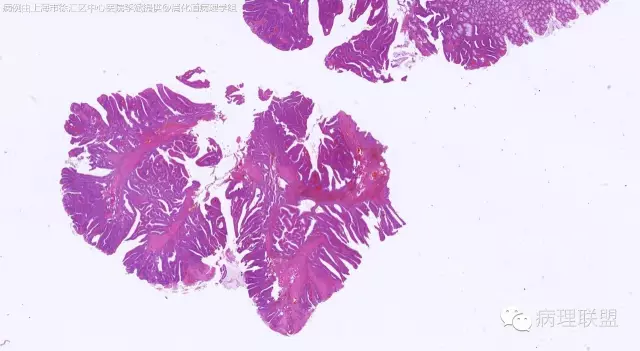

男,64岁,距肛门口45cm息肉大体:灰白结节2*2*1cm(病例由上海市徐汇区中心医院 李斌 提供,致谢!)

管状~绒毛状腺瘤伴低级别上皮内瘤变,黏膜下层部分腺体破裂黏液外溢伴黏液糊形成。

本例部分腺体异位到黏膜下层。